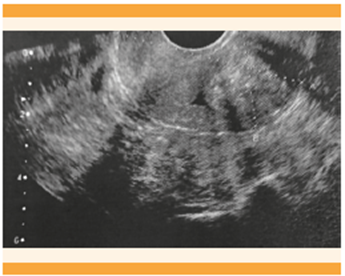

Está demostrado que la ecografía transvaginal tiene una sensibilidad y especificidad similares para diagnosticar adenomiosis cuando se compara con la resonancia magnética nuclear. 1,26 En la actualidad, para el diagnóstico de adenomiosis se utilizan los criterios del grupo MUSA, 27 en donde dos o más criterios son por demás sugerentes de adenomiosis. Los criterios son: engrosamiento miometrial asimétrico, quistes miometriales, islas hiperecogénicas, sombreado en forma de abanico, líneas y brotes subendometriales ecogénicos, vascularización translesional, cuando haya una zona de unión irregular y una zona de unión endometrial interrumpida. A pesar de lo anterior, aún se está trabajando en un consenso internacional que pueda definir un sistema de clasificación de adenomiosis que permita fenotipar el trastorno de una manera estandarizada. 1 Figura 6